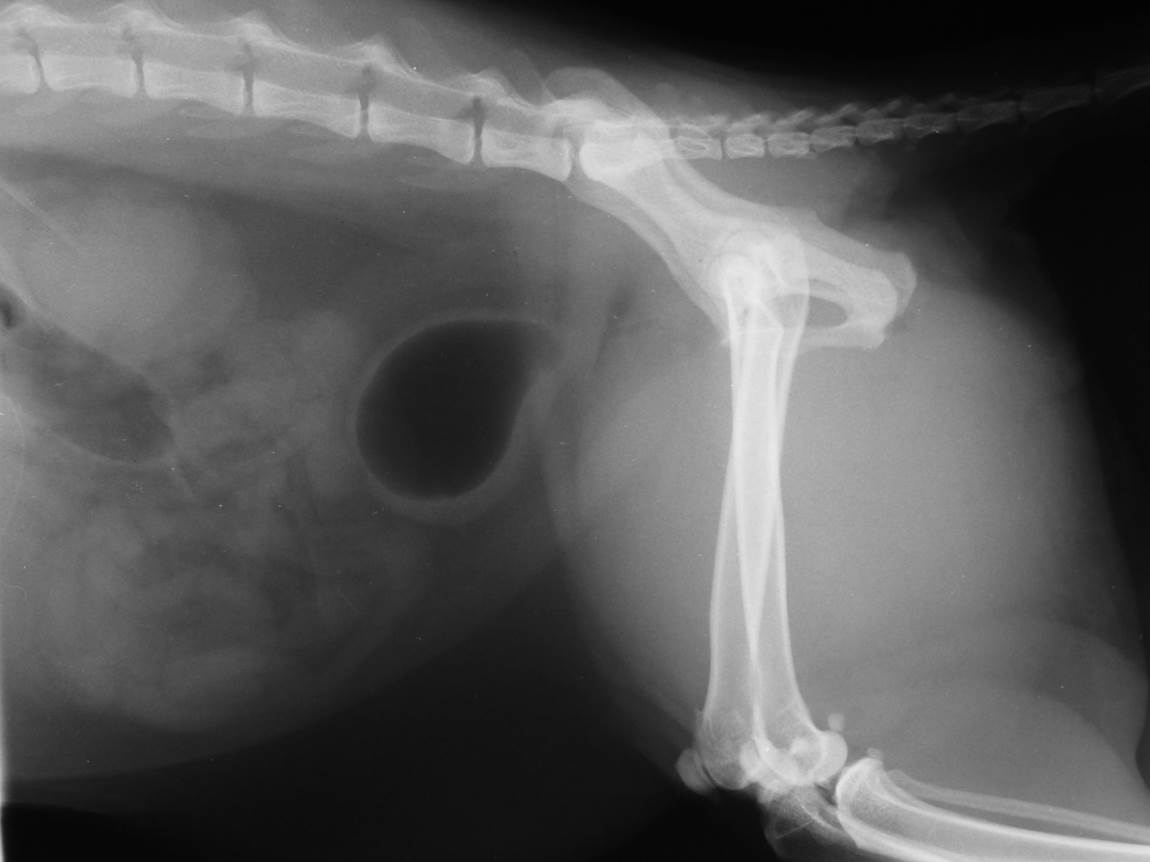

Case Beaver

Discuss this case?

•DCC and retrograde urethrogram

–poor quality urethrogram, poor filling of urethra, air bubbles ++. This study is important to rule out strictures, urethral plug, calculi.

•Bladder has identical appearance on both films

–small (likely not possible to distend further or at least not safely)

–thickened wall

–repeat retrograde to rule out stricture/urolith but doesn’t seem obstructed

–urinalysis especially for urine culture in case UTI following recent catheterisation during last episode of clinical signs

•Diagnosis: likely to be FLUTD, idiopathic cystitis